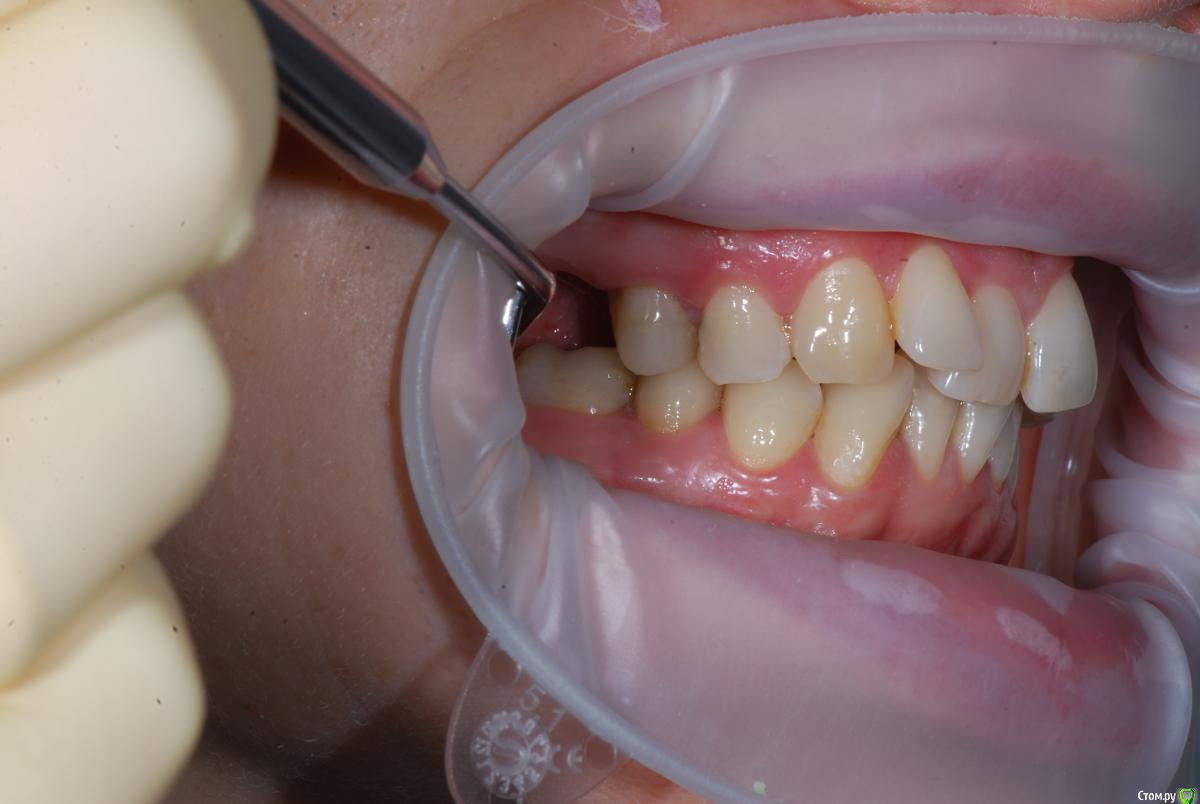

Afffinity Опубликовано 13 декабря, 2016 Автор Поделиться Опубликовано 13 декабря, 2016 Вот именно в чем в принципе сомневаетесь? и на моделях надо указывать анатомический центр, тогда сразу понятнее станет чего и куда и на сколько. ну Вы хотя бы свои мысли озвучили бы, расчет трг, характер асимметрии (в каком положении головки, что на КТ?) ... полностью Вам не распишут план, вопросы более конкретные попробуйте задать для коллегЕсли кратко то по расчетам ТРГ 2й скелетный класс, в цифрах завтра распишу. Прошу прощения что сразу не выложил. 2е, смущает смещение центральной линииПланируем установить систему Damon Q. Самый главный вопрос, возмножо ли в данном случае обойтись без удаления премоляров? Ссылка на комментарий